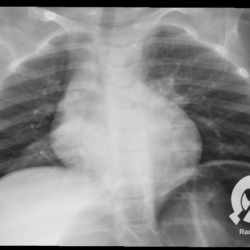

Os agentes etiológicos infecciosos são variados (bactérias, vírus, fungos, parasitas…), mas o que ocorre nos pulmões durante uma infecção por qualquer tipo de agente é a substituição do ar alveolar por secreção (pus, muco, eventualmente sangue ou necrose…) e com isso a manifestação radiográfica vai ser a mesma já que todas estas secreções apresentam a mesma densidade radiográfica: partes moles.

E o nome dado a esta alteração radiográfica que corresponde à substituição do ar alveolar por líquido é a consolidação alveolar.

Uma consolidação alveolar é, por definição, uma opacidade (imagem densa, branquinha) homogênea ou às vezes heterogênea (pela presença de calcificações ou cavidades), de limites mal definidos, exceto quando toca a pleura da parede ou das cissuras pulmonares. É um termo usado tanto em radiografia, como em tomografia computadorizada. Na tomografia, um outro termo é usado: vidro fosco, que é uma opacidade (branquinha mas não tanto como a consolidação), que borra o pulmão mas deixa ver os vasos de permeio (igual bigode de adolescente: dá pra ver todo o fundo).

Nós vamos mostrar aqui um pequeno apanhado de pneumonias de variados agentes, em diversos segmentos e lobos pulmonares, com extensões variadas. O objetivo é identificar o padrão radiológico de consolidação alveolar e não determinar o agente infeccioso, isso vai ser assunto para mais adiante. Aliás já antecipo que é fundamental saber localizar a lesão, porque alguns destes bichos gostam de determinados segmentos, alguns tumores também têm as suas preferências, então localização é fundamental. Se localização não fosse importante, um apartamento na beira do mar sairia o mesmo preço de um apartamento de frente pra BR-101, concordam?

Seguem alguns dos nossos casos de pneumonia para vocês treinarem os olhos e não se apavorarem nos plantões.